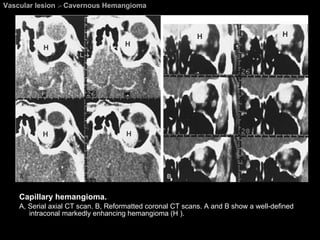

Cavernous Hemangioma M/C orbital vascular tumor in adults. Most often in women (60%–70%) between the ages of mean age, 43–48 years. Slowly progressive enlargement.  Histologically, composed of large, dilated vascular channels (sinusoid-like spaces) lined by thin, attenuated endothelial cells. A distinct fibrous pseudocapsule.

Cavernous Hemangioma CT and MR imaging; May be located anywhere in the orbit but frequently (83%) occur within the retrobulbar muscle cone. Uncommonly, an intramuscular hemangioma may occur. Well-defined masses.  Variable contrast enhancement.  Always respect the contour of the globe ( until ruptured ).  Orbital bone modeling is not uncommon.

Vascular lesion  >  Cavernous Hemangioma Capillary hemangioma.  A, Serial axial CT scan. B, Reformatted coronal CT scans. A and B show a well-defined intraconal markedly enhancing hemangioma (H ).